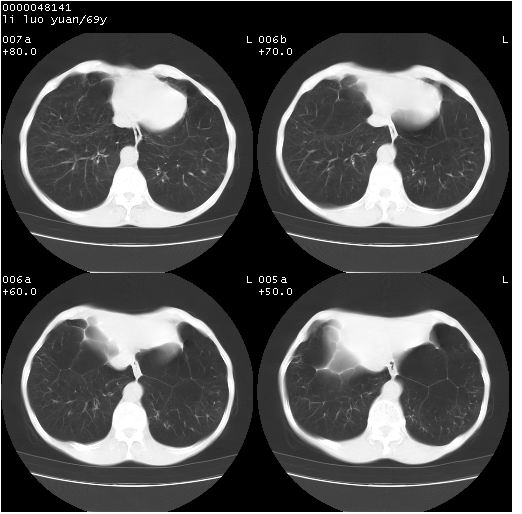

临床资料:老年患者,咯血、消瘦

影像表现:桶状胸,双肺纹理纤细、紊乱,透过度增高,肺野内可见多发、散在、大小不等的无壁高透过影,右肺中叶外侧段分叶样软组织占位,左上肺纤维索条样密度影,相应层面左侧胸腔轻度萎陷,纵隔左移。

影像诊断:1、慢支、肺气肿、双下肺野肺大泡形成

2、左上肺陈旧性肺结核

3、右肺中叶外侧段占位 考虑肺ca可能性较大、建议增强及痰检脱落细胞